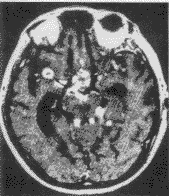

2.顱腦CT掃描 腦膿腫的CT表現依膿腫發展階段而異。急性化膿性腦炎階段 病灶表現為邊界模糊的低密度區 不強化。化膿與膿腫壁形成期,在低密度區周圍可顯示等密度膿腫壁 膿腫壁可輕度強化,強化厚度多不均勻,膿腫較小時,可呈結節狀強化,強化厚度多不均勻,膿腫較小可呈結節狀強化 膿腫周圍有不規則腦水腫帶,多較顯著 CT不僅可以確定膿腫的存在、位置、大小、數目、形狀及其周圍腦組織水腫情況 而且可幫助選擇治療方法和確定手術時機。

外傷性腦膿腫CT圖如膿腫淺在,周圍蛛網膜下腔已閉鎖且伴有開放性傷口或局部骨髓炎者,可行切開引流術,但還需注意清除膿腫內或其附近的碎骨片等異物。膿腫穿刺及置管引流適用於腦深部,重要功能區以及散在的多發膿腫;病程短、膿腫壁薄且不含異物者;另外對體質過弱或已有腦疝形成而無開顱手術條件時,穿刺引流可做暫時性治療措施。